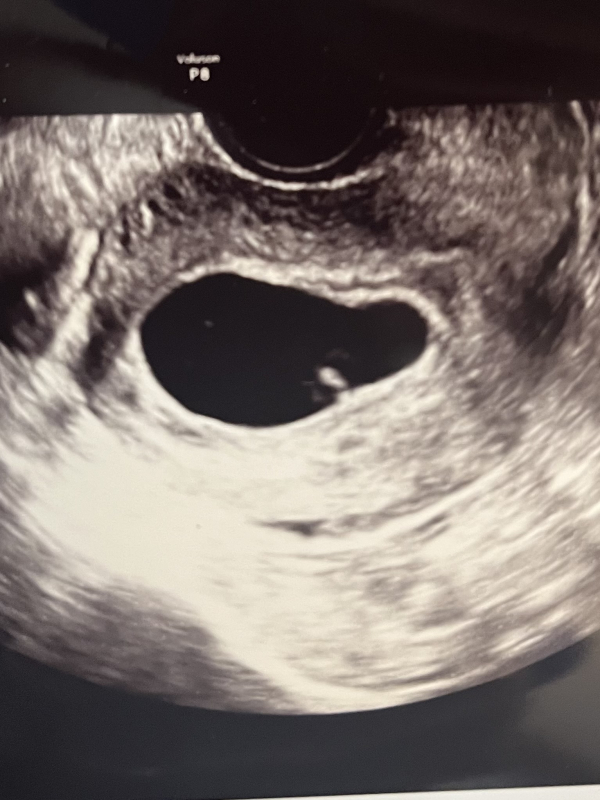

エコー写真も念の為添付させていただきます。

1枚目は6wのもので、2枚目は8wのものです。

最終月経日から計算して8w1dです。 6w0dに初診で胎嚢が14.4mm、GA 4w5d、胎芽が小さく見えていました。

昨日二回目の診察で8w0d、胎嚢は大きくなっていて2?mm程(細かい数字は曖昧です) 胎芽が4.5mmという事で、週数の割に胎芽が小さく、心拍が確認できませんでした。